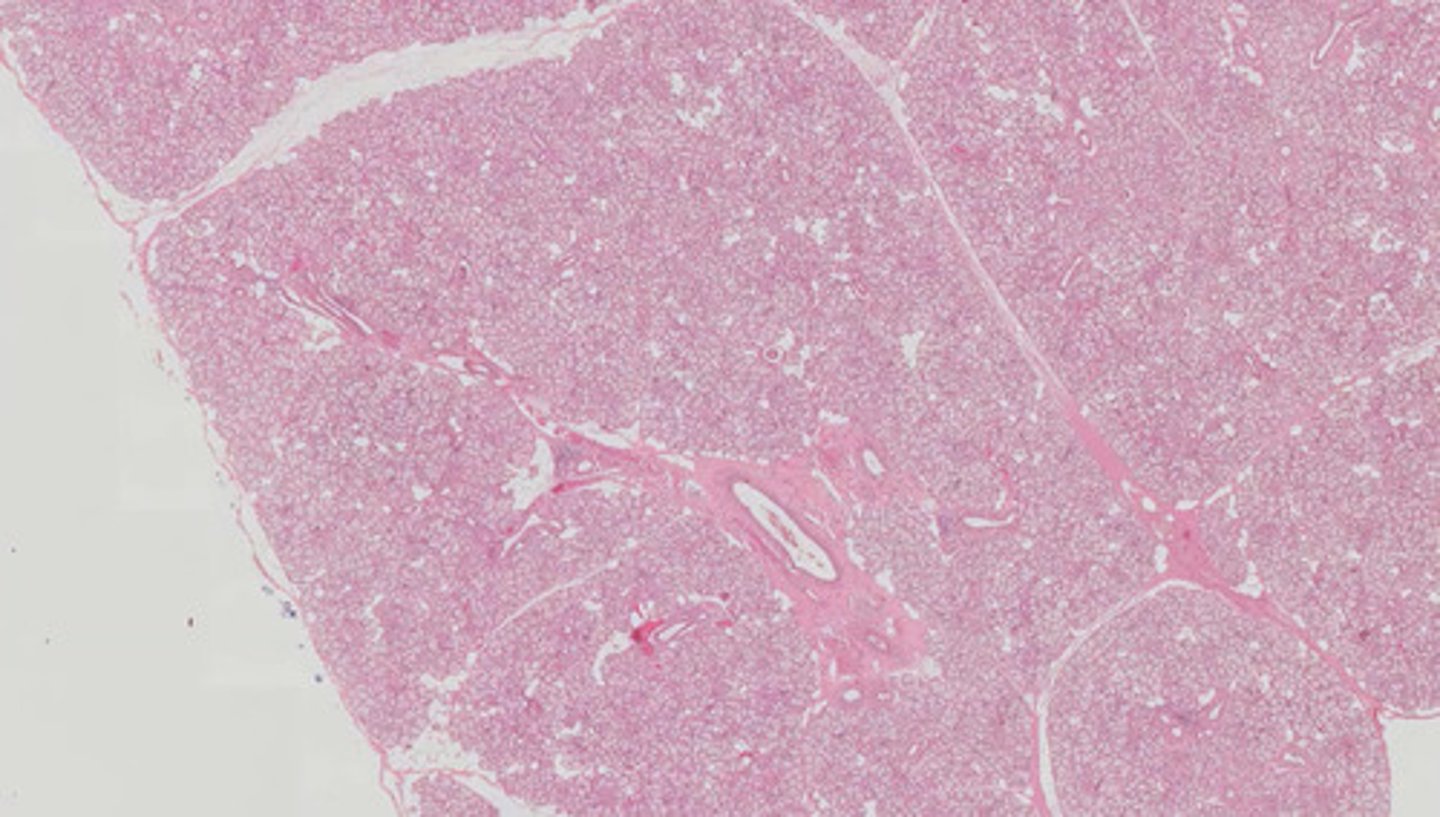

Śledziona (H+E)